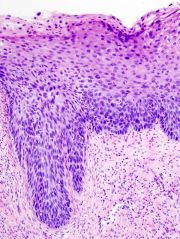

| 2021年7月26日 (一) 18:21 | Cervical intraepithelial neoplasia (4) CIN3.jpg (文件) |  |

130 KB | 77921020 | Uploaded with SimpleBatchUpload | 1 |